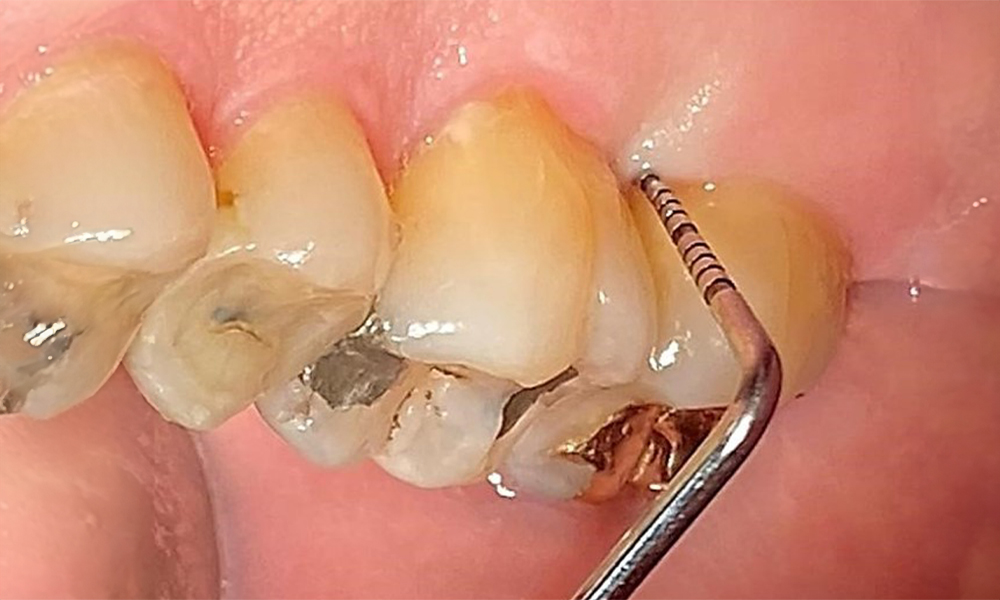

Probing to document the findings in tooth 27 mesiopalatal.

Fig. 8: Probing to document the findings in tooth 27 mesiopalatal. © Dr R. Krapf